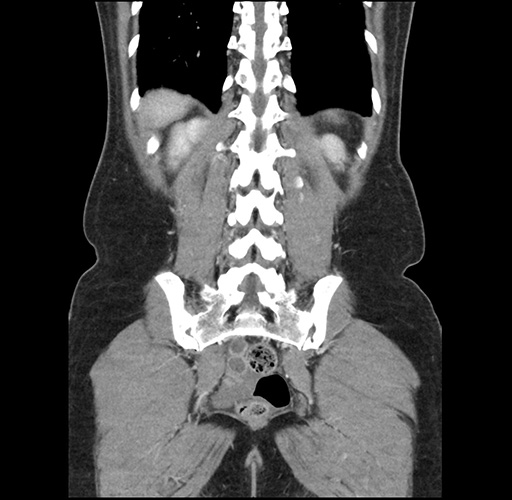

Left lateral sectionectomy [case 12]

Imaging Analysis

Look through the patient's CT scan to identify any areas of concern for the necessary procedure.

Based on your CT findings, which issue(s) would give reason for "planned slowing down moment(s)" in this case?

Considering a standard left lateral sectionectomy procedure, what step(s) of the operation would you do differently in this case ?